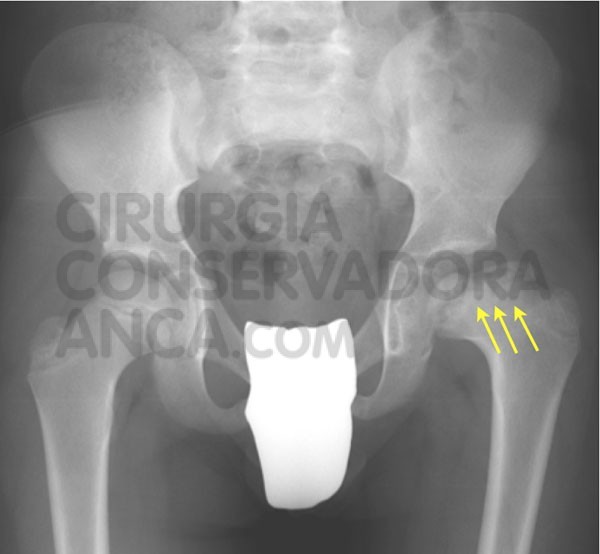

Perthes Disease Hip Preserving Surgery